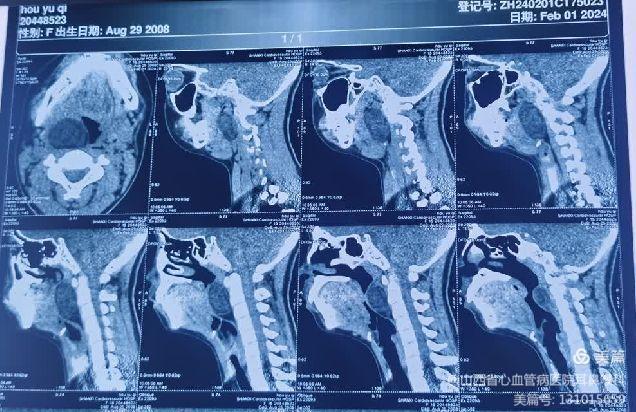

患儿就诊时,自觉偶有憋气及咽痛。张浩杰主任第一时间接诊,经过仔细查体、喉镜和颈部影像学CT与MRI检查后,发现患儿咽腔明显受压,口咽部椎前间隙巨大肿瘤。

该例肿瘤生长部位特殊,位于咽部椎前间隙,周围神经血管丰富,手术风险较大。然而,如果不及时治疗,肿瘤会继续增大,压迫周围组织,导致呼吸困难、吞咽困难等症状,严重时甚至危及生命。